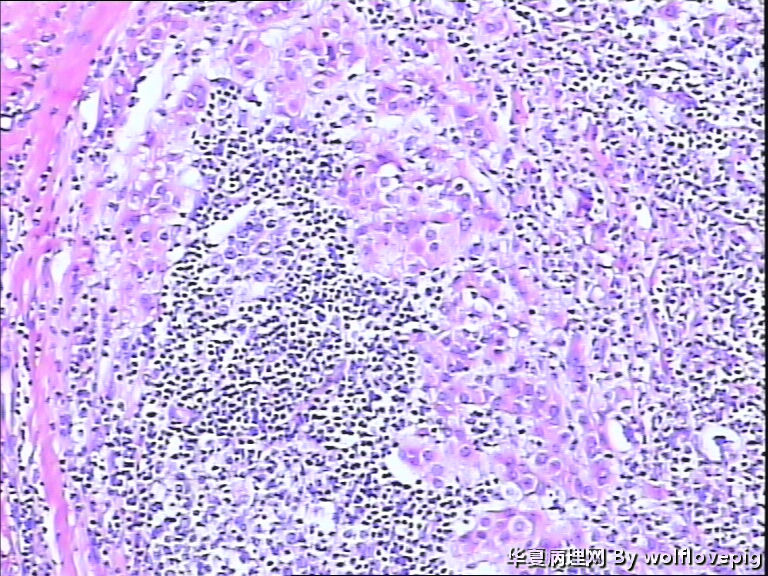

女,60y,发现右乳包块6+月。

灰白不整形组织一块:3*2*1.5cm,切面有一灰白区域,边界欠清,质韧。

图2